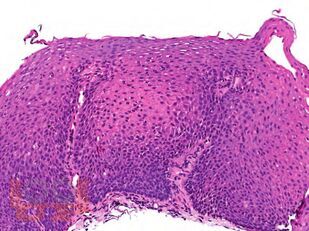

Руководство по прижизненной патолого-анатомической диагностике болезней органов пищеварительного тракта представляет собой стандартизированный свод правил вырезки и гистологической обработки материала по международным стандартам с расчетом нормативов затрат рабочего времени и материальных ресурсов. Опухолевая патология изложена в руководстве только в аспекте дифференциальной диагностики и в том объеме операционно-биопсийного материала, который наиболее часто встречается в патолого-анатомической практике в медицинских организациях неонкологического профиля. Приведены опорные диагностические макро- и микроскопические признаки, в основу которых положены современные классификации, международные протоколы патолого-анатомического исследования биопсий, мнения экспертов, а также личный опыт авторов.

Руководство снабжено схемами, рисунками, таблицами.